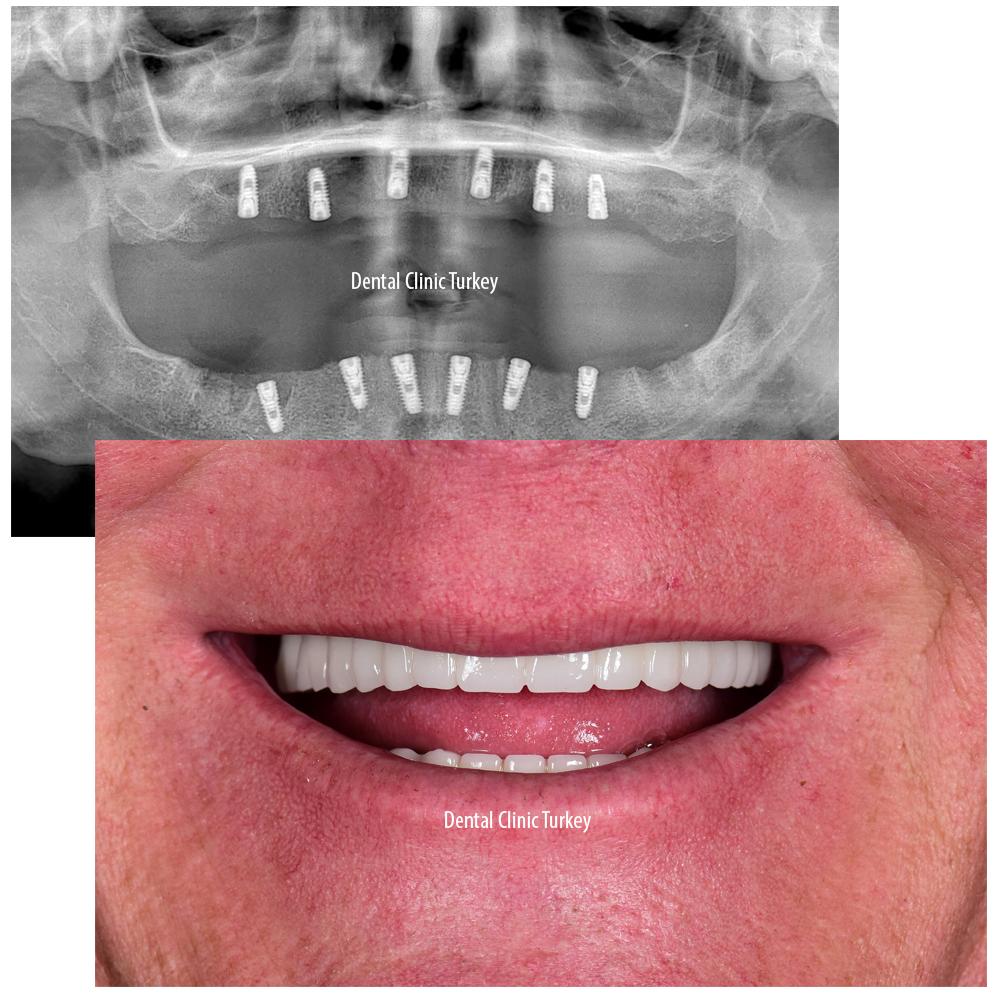

When considering the All-on-Six implant procedure, it’s important to grasp how this innovative dental solution works. Essentially, six strategically placed titanium implants are anchored into the jawbone, providing a strong foundation for a full set of fixed teeth. This design offers enhanced stability and longevity compared to traditional dentures or fewer implants. The process is typically completed in a series of phases including consultation, implant placement, healing, and final prosthesis fitting. Each stage is carefully planned to maximize comfort, function, and aesthetics.

A: Always ask about your dentist’s specific experience with All-on-Six implants, including the number of procedures performed and success rates. Request before-and-after photos and, if possible, testimonials from UK patients who have undergone the treatment.